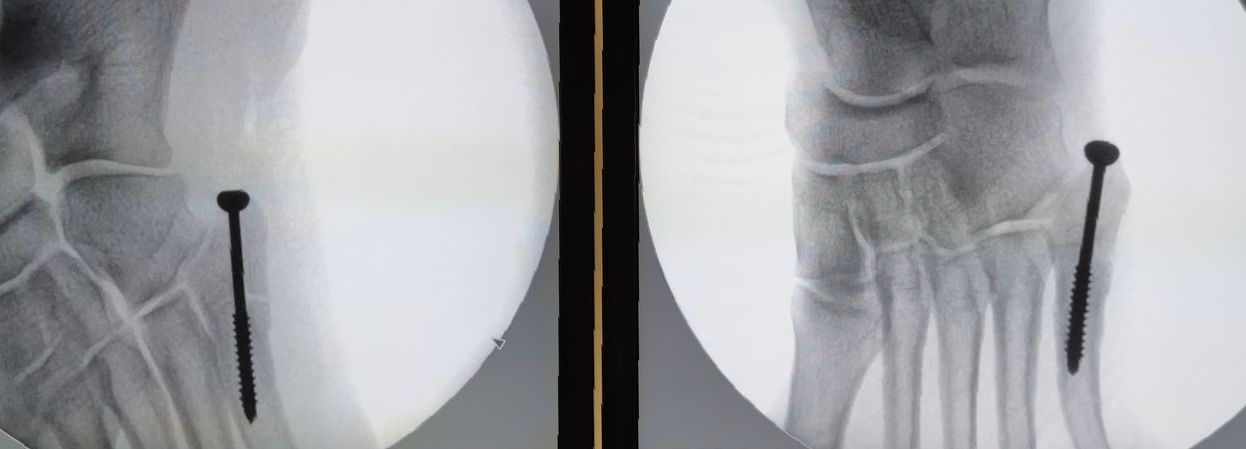

Cirurgia Artroscópica

Patologia do Tornozelo